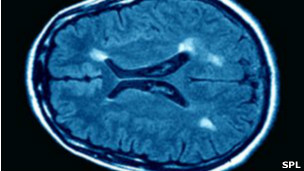

در بیماری ام اس، سیستم دفاعی بدن علیه سیستم عصبی خود وارد عمل می شود و باعث می شود ماهیچه ها از کار بیافتند.

کسانی که به بیماری ام اس مبتلا هستند برای مدت زمانی علائم این بیماری را حس نمی کنند اما این علائم به طور ناگهانی دوباره ظاهر می شوند.